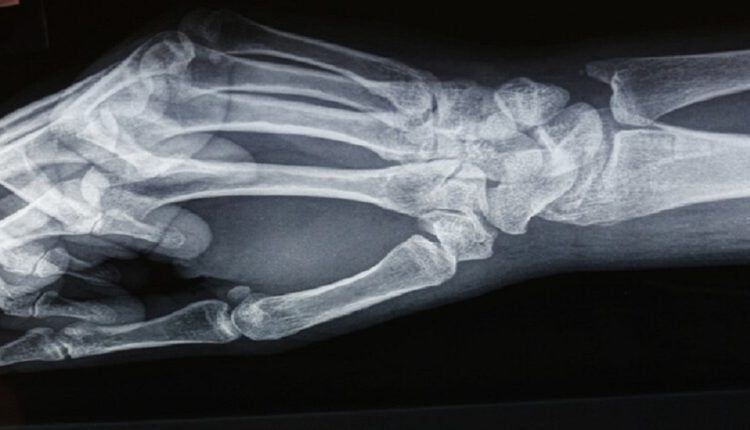

ضمادة “كهروضوئية” لتسريع التئام العظام المكسورة

أعرب سيونغ-بوم هونغ، أحد الباحثين الرئيسيين في الدراسة، عن حماسه بشأن هذا التطوير، قائلاً: “لقد نجحنا في تطوير مادة مركبة كهروضوئية تعتمد على هيدروكسي أباتيت. ويمكنها العمل بمثابة “ضماد للعظام” بسبب قدرتها على تسريع عملية تجديد العظام”.